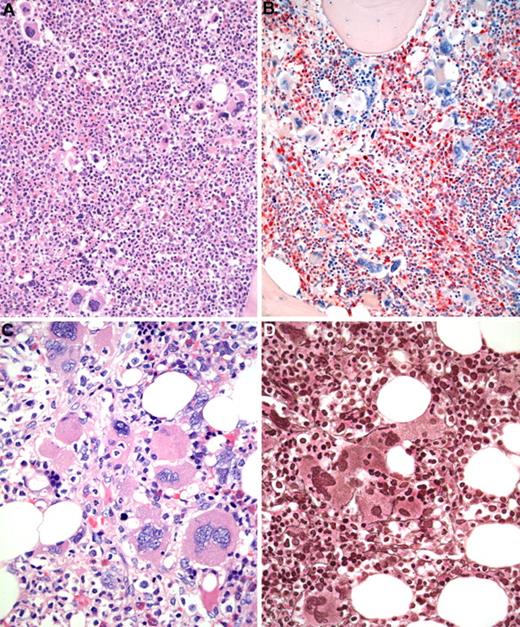

BM biopsy histology in early PMF in low-power (×170) or medium-power (×350) field. (A) Survey with hematoxylin and eosin-stained section shows increase in age-matched cellularity and conspicuous clusters of atypical megakaryocytes. (B) Chloroacetate esterase reaction discloses that increased cellularity is mostly the result of neutrophil granulopoiesis (red) and prominent clustering of large, abnormal megakaryocytes with paratrabecular dislocation. (C) PAS staining reveals not only loose and tight clustering but also striking abnormalities of megakaryocytes showing large hyperchromatic-hypolobulated, cloud-like nuclei. (D) Reticulin stain displays minimal increase with a fine network of fibers between the clustered abnormal megakaryocytes. Images were acquired using Zeiss Axioplan 2, 20×/0.50 and 40×/0.60 EC PlanNeofluar.

BM biopsy histology in early PMF in low-power (×170) or medium-power (×350) field. (A) Survey with hematoxylin and eosin-stained section shows increase in age-matched cellularity and conspicuous clusters of atypical megakaryocytes. (B) Chloroacetate esterase reaction discloses that increased cellularity is mostly the result of neutrophil granulopoiesis (red) and prominent clustering of large, abnormal megakaryocytes with paratrabecular dislocation. (C) PAS staining reveals not only loose and tight clustering but also striking abnormalities of megakaryocytes showing large hyperchromatic-hypolobulated, cloud-like nuclei. (D) Reticulin stain displays minimal increase with a fine network of fibers between the clustered abnormal megakaryocytes. Images were acquired using Zeiss Axioplan 2, 20×/0.50 and 40×/0.60 EC PlanNeofluar.